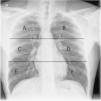

Con el fin de graduar la extensión de la afectación pulmonar (índice de gravedad radiográfico), cada pulmón se dividió en tres campos separados por dos líneas horizontales: una superior a la altura del borde inferior del cayado aórtico y otra inferior a la altura de las venas pulmonares13,15 (fig. 2). La cuantificación de la extensión de la afectación pulmonar se obtuvo sumando la puntuación en cada campo pulmonar (0=normal y 1=con afectación), obteniéndose una puntuación global para ambos pulmones entre 0 y 6.

Radiografía de tórax con la división pulmonar en seis campos que se ha empleado en nuestro estudio para la valoración de la distribución de los hallazgos radiológicos. La línea horizontal superior pasa por el borde inferior del arco aórtico y la línea horizontal inferior pasa a la altura de las venas pulmonares inferiores. A y B) Campos superiores. C y D) Campos medios. E y F) Campos inferiores.